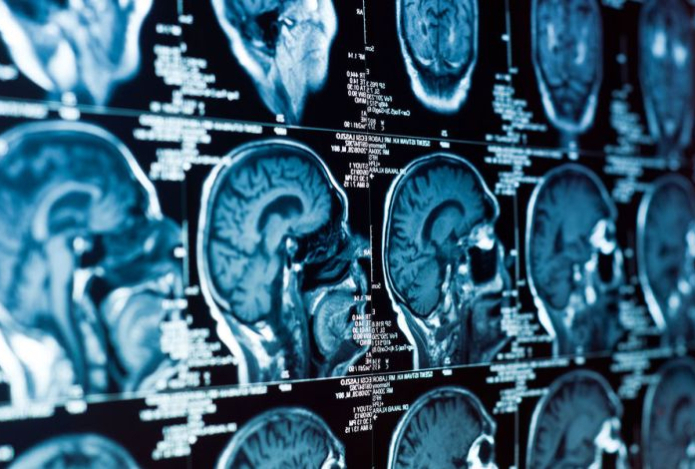

Ученые из Университета Флориды и колледжа Провиденс установили, что жизнь в социальной изоляции оказывает на мозг стареющих крыс эффект, схожий с токсическим воздействием, ускоряя снижение когнитивных функций, передает Sports.kz со ссылкой на Gazeta.ru.

У крыс, которые жили в одиночестве, начали проявляться серьезные нарушения памяти и когнитивной гибкости. По словам ученых, такой эффект был схож с результатом отравления токсинами. Выполнение умственных задач для животных из второй группы требовало больших усилий — нейроны передней поясной коры активировались интенсивнее, что свидетельствовало об истощении ресурсов.

В то же время у социализированных крыс когнитивные способности сохранялись на уровне молодых особей. В гиппокампе грызунов из второй группы также не наблюдалось значительного снижения активности в области CA3, ключевой для памяти и обучения.